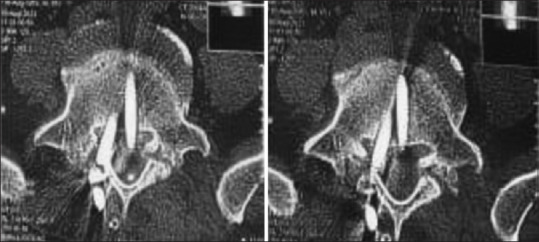

Results: In our study, we included 102 patients including 62 (60.7%) males and 40 (39.2%) females. More than half of patients were young in the age group of 20-50 years. Our study population had a varied etiology with 43.1% of patients having vertebral column instability due to trauma. The other etiologies were spondylolisthesis and lumbar canal stenosis (39.2%), Pott's spine (11.7%), tumors (2.9%), and osteoporotic fractures (2.9%). Majority of patients (44.1%) presented with lower backache with radiculopathy. All the transpedicular screws inserted were evaluated by C-arm to assess for screw fixation. In the first year of our study, an average of 4 anteroposterior (AP) and 4 lateral C-arm X-ray shots were taken per screw placement. In the next year, an average of 3 AP and 3 lateral shots and finally in the last year of our study only 2 AP and 2 lateral C-arm X-ray shots were taken per screw placement. Out of 650 screws placed, 4 screws were identified to cause breach with maximum breaches in the lumbar spine fixation. In dorsal spine fixation, there was 1 lateral breach at D10. In lumbar spine fixation, there were 3 breaches: two medial one each at L4 and L5 and one anterior at L2 level. The various complications include wound infection, temporary and permanent neurological deficit, screw breakage, screw misplacement, cerebrospinal fluid leaks, nonunion, and spinal epidural hematoma.